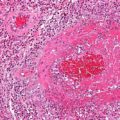

On microscopy arteriosclerosis appears as pink hyaline around the circumference of the vessel.

Hyperplastic arteriolosclerosis thickens the artery wall by causing smooth muscle hyperplasia in an “onion-skin” pattern.

Fibrinoid necrosis of the vessel wall may also be seen in hyperplastic arteriolosclerosis.